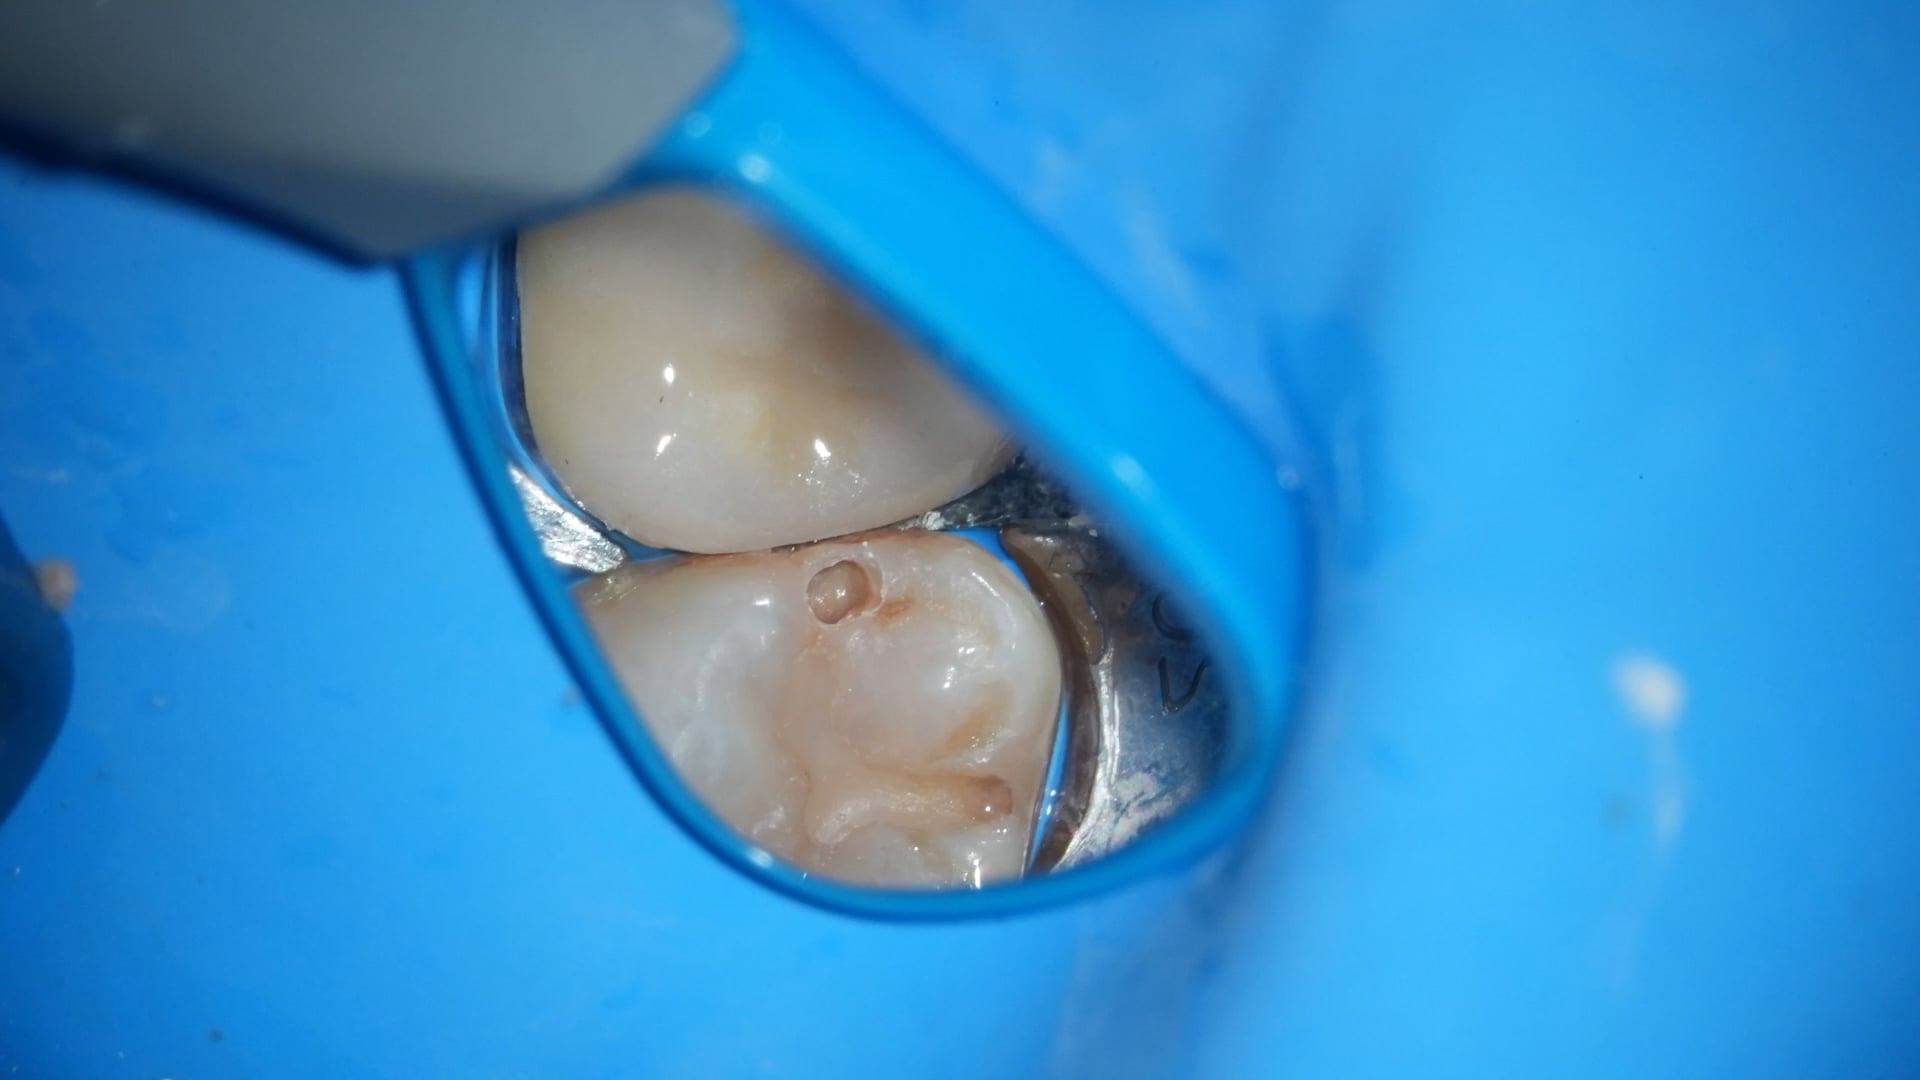

術前

う蝕除去

以前のCRを除去し、う蝕を確実に取り除く。う蝕除去後はサンドブラストとエアスケーラーで窩洞と周囲を処理し、確実な接着環境を整える。

5倍速を使用することでブレを抑え、精度の高い処置が可能となる。小さく長いバーを選び、歯間離開を併用することで切削量を最小限にし、視野が確保しやすくなることで、操作性も向上する。